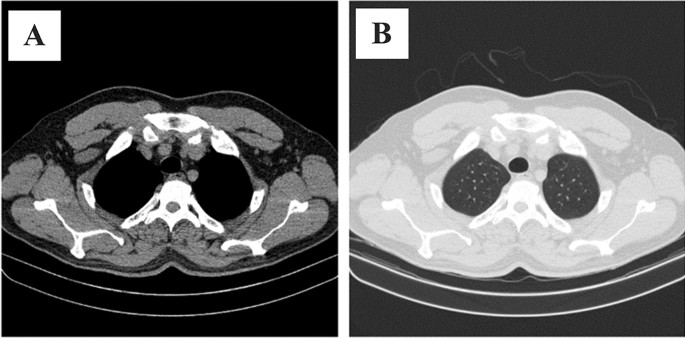

In this section, we propose several models that benefit from the transfer learning technique to detect COVID-19 in CT scan slides. Although the 2D-COVID-MAH-CT dataset exclusively contains COVID-19 samples, in order to effectively train the models for the classification task, it is necessary to incorporate normal CT scans. In order to achieve this, we incorporated normal images that were obtained from30, which were taken from Iranian patients and therefore have the same distribution as our dataset. Specifically, we selected normal images from the first 50 patients in this dataset, resulting in a collection of 5216 normal images, all of which had a resolution of 512 × 512 (matching our dataset). However, the images in30 were provided with an abdomen view and therefore required transformation to a lung view before being utilized for the purpose of this study as demonstrated in Fig. 1A,B.

(A) a sample obtained from30 in its original abdomen view. (B) the same sample transformed into the lung view.